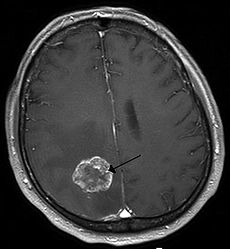

A brain tumor is an intracranial solid neoplasm, a tumor (defined as an abnormal growth of cells) within the brain or the central spinal canal.

Brain tumors include all tumors inside the cranium or in the central spinal canal. They are created by an abnormal and uncontrolled cell division, normally either in the brain itself (neurons, glial cells (astrocytes, oligodendrocytes, ependymal cells, myelin-producing Schwann cells), lymphatic tissue, blood vessels), in the cranial nerves, in the brain envelopes (meninges), skull, pituitary and pineal gland, or spread from cancers primarily located in other organs (metastatic tumors).

Any brain tumor is inherently serious and life-threatening because of its invasive and infiltrative character in the limited space of the intracranial cavity. However, brain tumors (even malignant ones) are not invariably fatal. Brain tumors or intracranial neoplasms can be cancerous (malignant) or non-cancerous (benign); however, the definitions of malignant or benign neoplasms differs from those commonly used in other types of cancerous or non-cancerous neoplasms in the body. Its threat level depends on the combination of factors like the type of tumor, its location, its size and its state of development. Because the brain is well protected by the skull, the early detection of a brain tumor only occurs when diagnostic tools are directed at the intracranial cavity. Usually detection occurs in advanced stages when the presence of the tumor has caused unexplained symptoms.

Primary (true) brain tumors are commonly located in the posterior cranial fossa in children and in the anterior two-thirds of the cerebral hemispheres in adults, although they can affect any part of the brain.